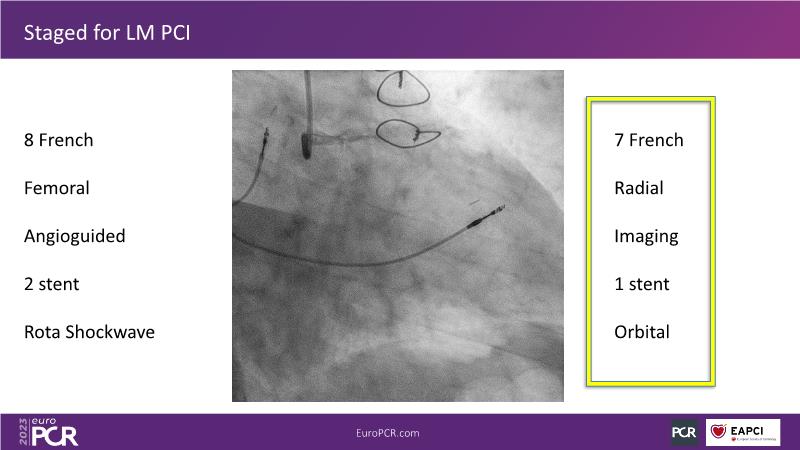

The aim of this session is to address the question of how to optimise outcomes for high-risk patients by analyzing two real-life cases for discussion: a distal calcified left main trifurcation and a high-risk PCI with orbital atherectomy.